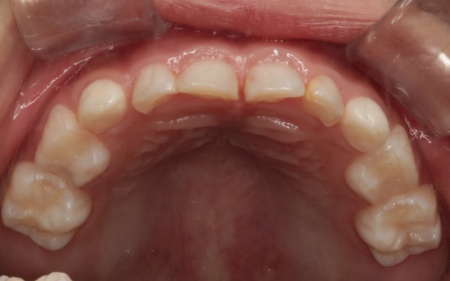

治療後

治療中は、スクリューを少しずつ回すことで顎の骨が徐々に横方向に拡大されていき、永久歯が生えるためのスペースを十分に確保することができました。

拡大治療が完了したあとは、顎の状態を安定させるためのリテーナー(保定装置)を装着し、治療を終了しています。